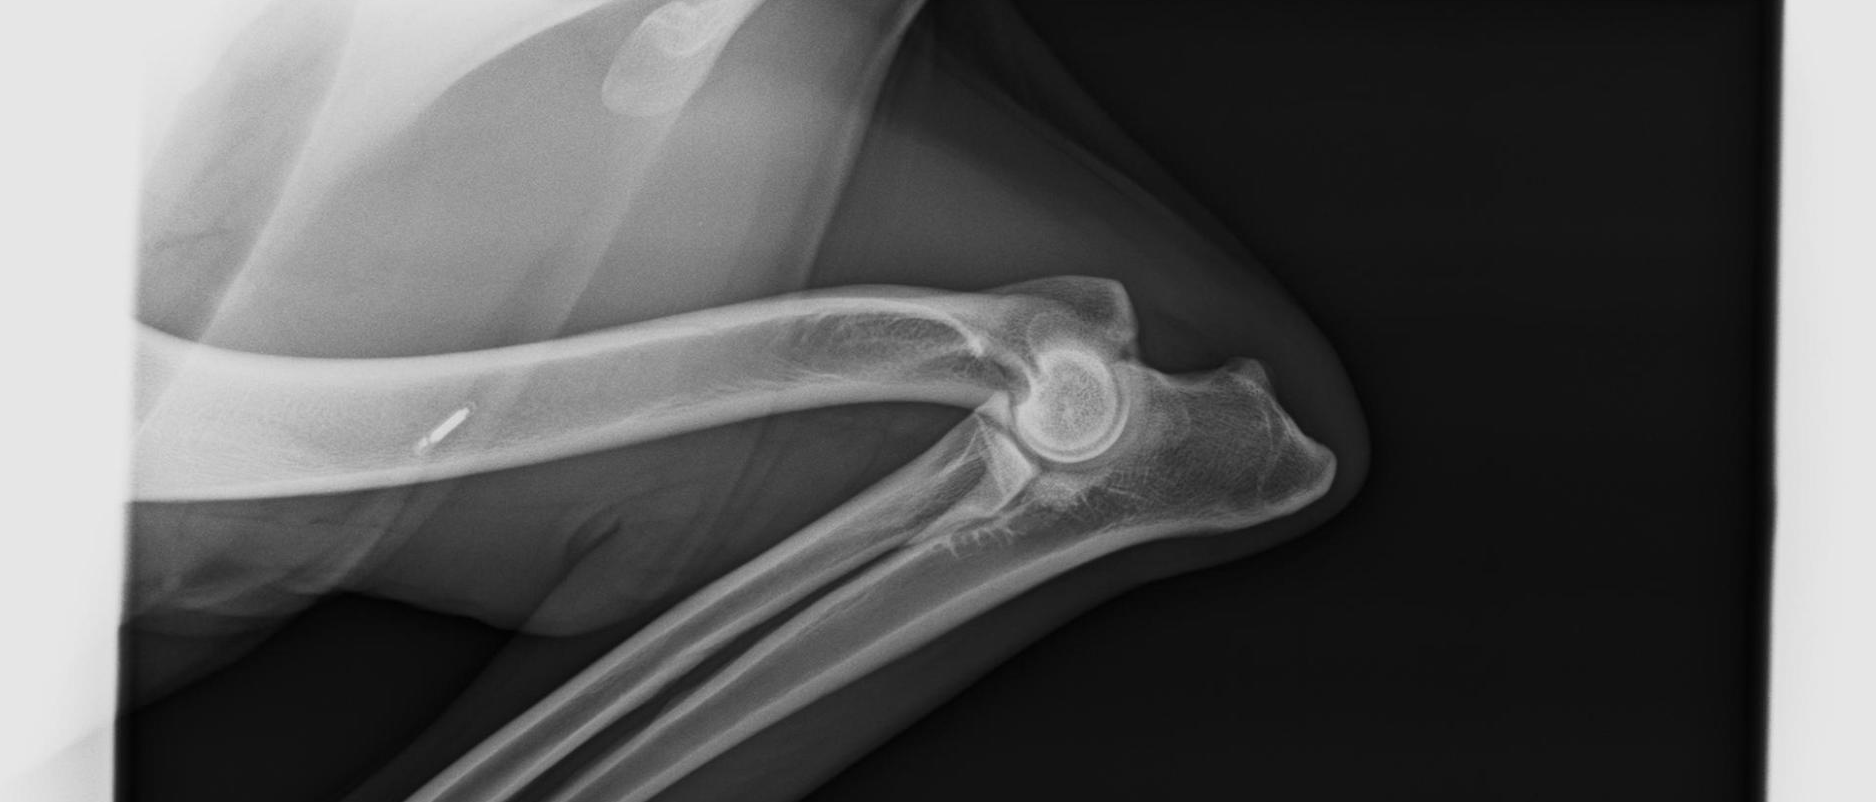

ED - Ellbogendysplasie

Die Ellenbogengelenksdysplasie (ED) ist ein chronisch verlaufender Krankheitskomplex des Ellenbogengelenks schnellwüchsiger Hunderassen. Die ED stellt eine vererbte Entwicklungsstörung des wachsenden Skeletts dar. Hohes Körpermassewachstum und Fütterungsfehler sind weitere begünstigende (prädisponierende) Faktoren. Die ED beginnt in der späten Wachstumsphase bei vier bis acht Monate alten Jungtieren mit einer schmerzhaften Veränderung des Gelenks und der gelenkbildenden Knochenteile (Osteoarthrose) mit Lahmheit. Der Bewegungsumfang des Ellenbogengelenks ist eingeschränkt. Frühzeichen sind Steifigkeit am Morgen oder nach Ruhepausen. Die Krankheit schreitet lebenslang fort und ist nicht heilbar, eine weitgehende Schmerzfreiheit kann aber in vielen Fällen erreicht werden.

Eine Ellbogendysplasie kann bei allen großwüchsigen Hunderassen auftreten. Die Häufigkeit des Auftretens beträgt bei einigen Rassen über 40 %.

Die ED wird polygenetisch (über mehrere Gene) vererbt. Der genaue Erbgang und die beteiligten Gene sind bislang nicht bekannt, so dass kein Gentest für die Erkrankung existiert. Der Nachweis kann daher bislang nur über die tierärztliche Beurteilung des Einzeltieres erfolgen, einige Hundezuchtverbände fordern eine Röntgenuntersuchung für Zuchttiere. Der Grad der Vererbbarkeit (Heritabilität) ist für Rüden größer als für Hündinnen und wird je nach Rasse und Population mit Werten zwischen 0,1 und 0,7 angegeben.

Die Röntgenbilder zeigen einen völlig gesunden Ellenbogen.